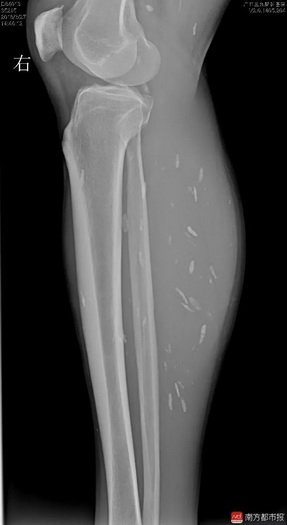

今年3月,刘宇连续两周头痛剧烈,走路不平稳,遂去广东三九脑科医院就医。据该院神经外六科主任吴杰介绍,患者的影像检查提示颅内多发占位病变,结合病史,考虑为颅内多发脑囊虫病。近日,吴杰主任为患者在全麻下行“左侧小脑囊虫占位切除术”。术后病理提示为脑囊虫病。除了头部,影像检查还提示,患者双下肢也有囊虫。

腿部特写或引不适,

可迅速下拉滑过

通讯员供图